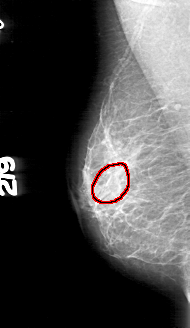

FILE: D_4166_1.RIGHT_MLO.OVERLAY

TOTAL_ABNORMALITIES 1

ABNORMALITY 1

LESION_TYPE CALCIFICATION TYPE AMORPHOUS DISTRIBUTION CLUSTERED

ASSESSMENT 0

SUBTLETY 2

PATHOLOGY BENIGN

TOTAL_OUTLINES 1

BOUNDARY

FILE: D_4166_1.RIGHT_CC.OVERLAY